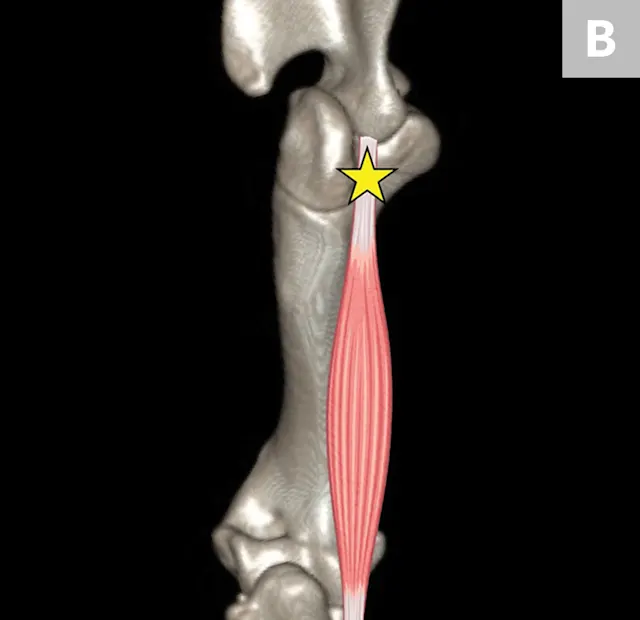

The iliopsoas muscle consists of the iliacus and psoas major muscle groups, which originate along the lumbar spine and ilium and insert on the lesser trochanter of the femur. Its main function is to flex and externally rotate the hip. Injury can occur secondary to an acute excessive force or repetitive use and/or trauma, resulting in a mild-to-severe pelvic limb lameness.7-10 Pain often can be elicited on examination by extension and internal rotation of the hip joint, abduction of the femur, and direct palpation of the muscle–tendon junction near the lesser trochanter.7-10 Because the femoral nerve runs through the iliopsoas muscle, some dogs that strain this muscle may also develop a peripheral neuropathy from compression of the nerve.8,9 Standard radiography can identify mineralization in the tendon, whereas ultrasonography, CT, and MRI are helpful for identifying early and subtle lesions and can help direct therapy (Figures 5 and 6).8-10 Mild-to-moderate acute lesions can often be treated with medical management (eg, rest, NSAIDs, physiotherapy, platelet-rich plasma injections).10 If the lesion is severe and results in fibrosis or contracture of the muscle, a partial tenectomy may be indicated.8,10